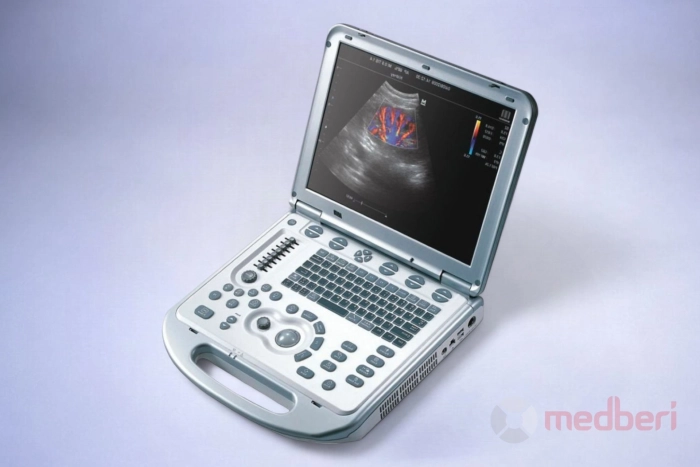

УЗИ аппарат Mindray M5

Mindray M5 — это портативный УЗИ-аппарат среднего класса, сочетающий передовые технологии и компактный дизайн, что делает его идеальным решением для мобильной диагностики и небольших медицинских учреждений. Аппарат обеспечивает высокое качество визуализации при проведении различных медицинских исследований, включая кардиологию, абдоминальные, сосудистые, акушерско-гинекологические и урологические обследования.

- Mindray M5 весит всего 6 кг, что делает его удобным для использования в условиях ограниченного пространства или при необходимости частого перемещения;

Mindray M5 — это надежный и удобный УЗИ-аппарат, который сочетает в себе мобильность, современный функционал и высокую производительность для качественной диагностики в различных областях медицины.